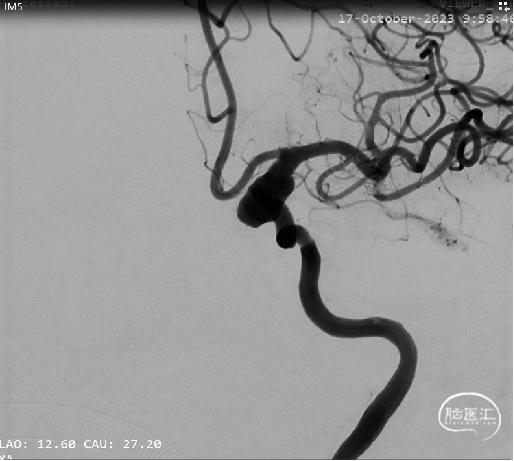

右侧颈内动脉造影:

左侧颈内动脉末端夹层动脉瘤、左侧大脑中动脉分叉部动脉瘤、右侧颈内动脉脉络膜前动脉处动脉瘤。

a.左侧颈内动脉末端夹层动脉瘤形状不规则且囊体较大,大脑中分叉部动脉瘤有一分支发出,这两处动脉瘤相对危险性高,此次优先处理;右侧脉前动脉瘤二期治疗。

b.左侧颈内动脉末端夹层动脉瘤呈不规则长条形改变,脉络膜前动脉在瘤体远端发出,若选用传统的弹簧圈栓塞治疗,则有可能出现分支闭塞,引起并发症,因此考虑使用血流导向装置密网支架覆盖载瘤动脉,避免出现分支血管闭塞。

术前测量左侧颈内动脉末端夹层动脉瘤长10mm,瘤体最宽处8mm,载瘤动脉近端血管直径约4.2mm,远端血管直径约3.5mm。拟选用Nuva®血流导向密网支架 TJED-D-4.5-30(预期血管直径长度:4.0mm*40mm)。